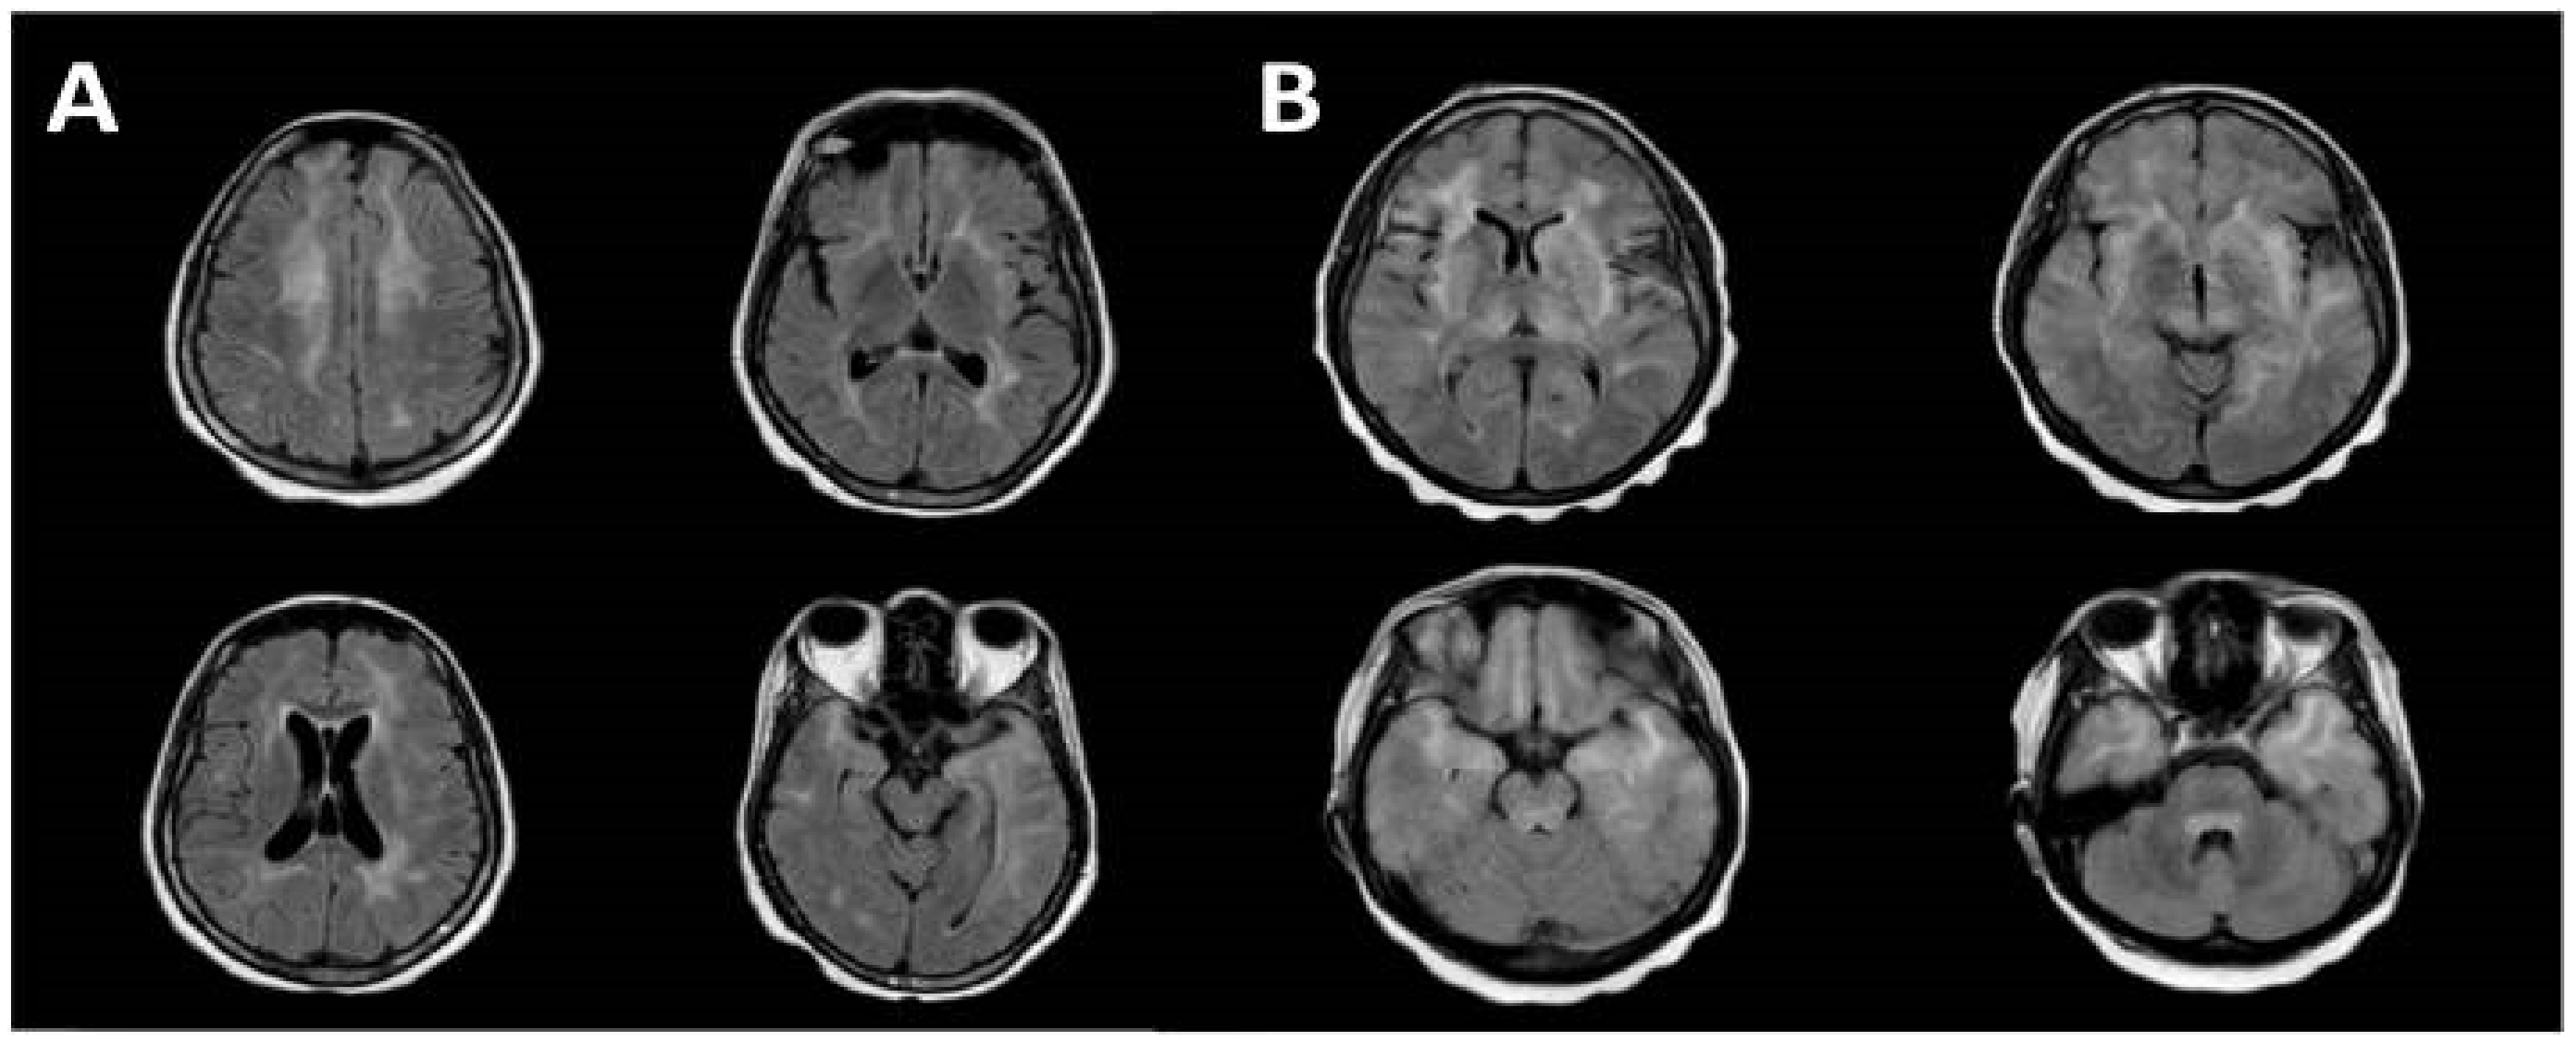

- Sakai, M.; Higashi, M.; Fujiwara, T.; Uehira, T.; Shirasaka, T.; Nakanishi, K.; Kashiwagi, N.; Tanaka, H.; Terada, H.; Tomiyama, N. MRI imaging features of HIV-related central nervous system diseases: Diagnosis by pattern recognition in daily practice. Jpn. J. Radiol. 2021, 39, 1023–1038. [Google Scholar] [CrossRef]